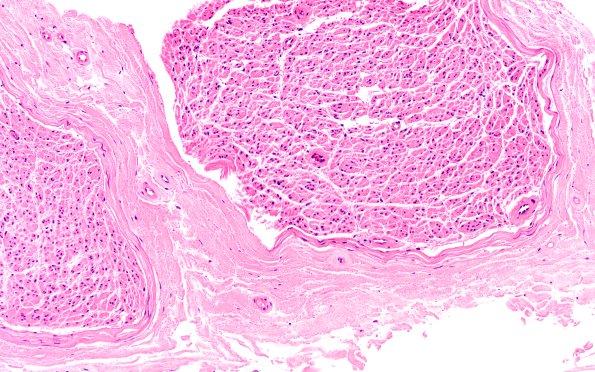

Washington University Experience | PERIPHERAL NEUROPATHY | 11 VASCULITIS - VASCULOPATHY | 2 Vasculopathy | 6A1 (Case 6) H&E 20X 1

Case 6 History ---- The patient is an 85-year-old man who presented with 6 months of progressive weakness in the right upper extremity and distal legs. EMG showed severe chronic sensorimotor axonal polyneuropathy. ---- 6A1,2 There is no evidence of vasculitis but there is evidence of endoneurial vascular thickening. (H&E)